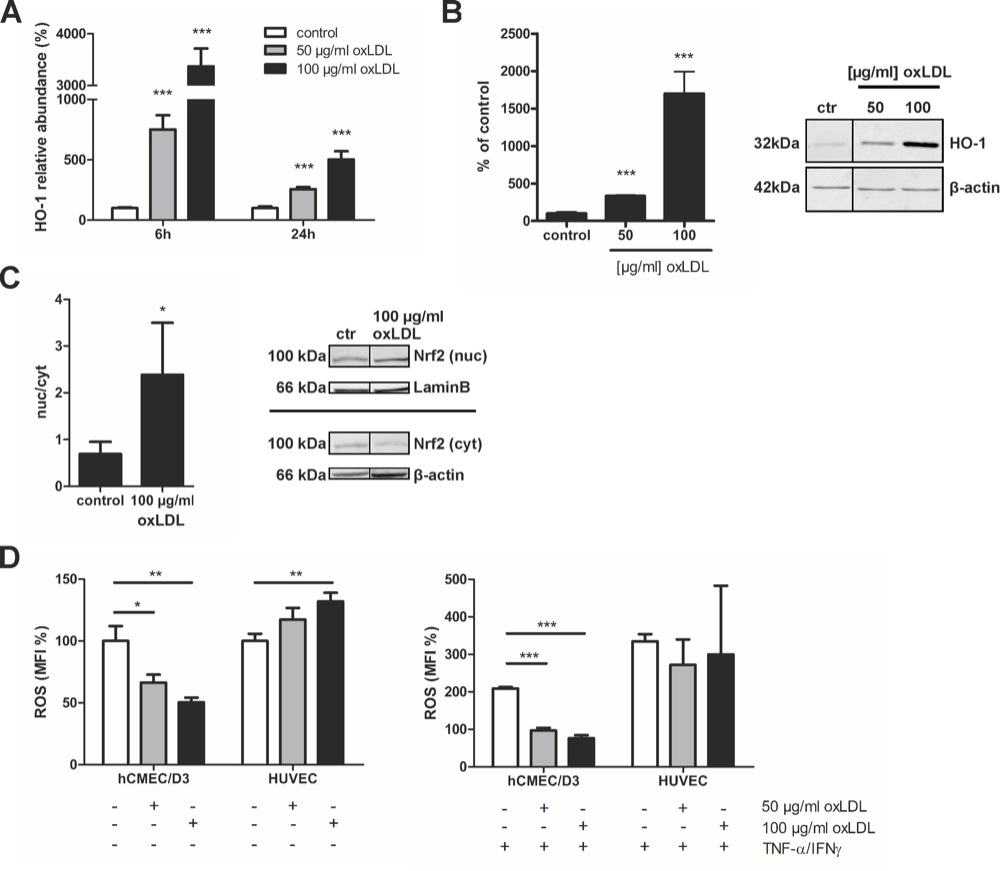

Chapter 3 Figure 4oxLDL protects brain endothelial (hCMEC/D3) cells from oxidative stress. A, HO-1 expression levels are increased after 6 and 24h (n=4). B, Quantification of HO-1 protein expression as measured by western blot, corrected for actin (n=3). C, Western blot analysis of nuclear and cytoplasmic fractions of brain endothelial cells corrected for laminB and β-actin, respectively, showed an increased nuclear presence of Nrf2 (n=4). D, oxLDL significantly reduced brain endothelial reactive oxygen species (ROS) production in untreated and immune-activated (TNFα/IFNγ) conditions (n=3). Expression data are presented as means ± SD. ROS production is presented as median fluorescent intensity (MFI) percentage compared to control ± SD. Statistical significance was determined by two-tailed Student’s t-test. *p < 0.05, **p < 0.001, ***p < 0.0001.